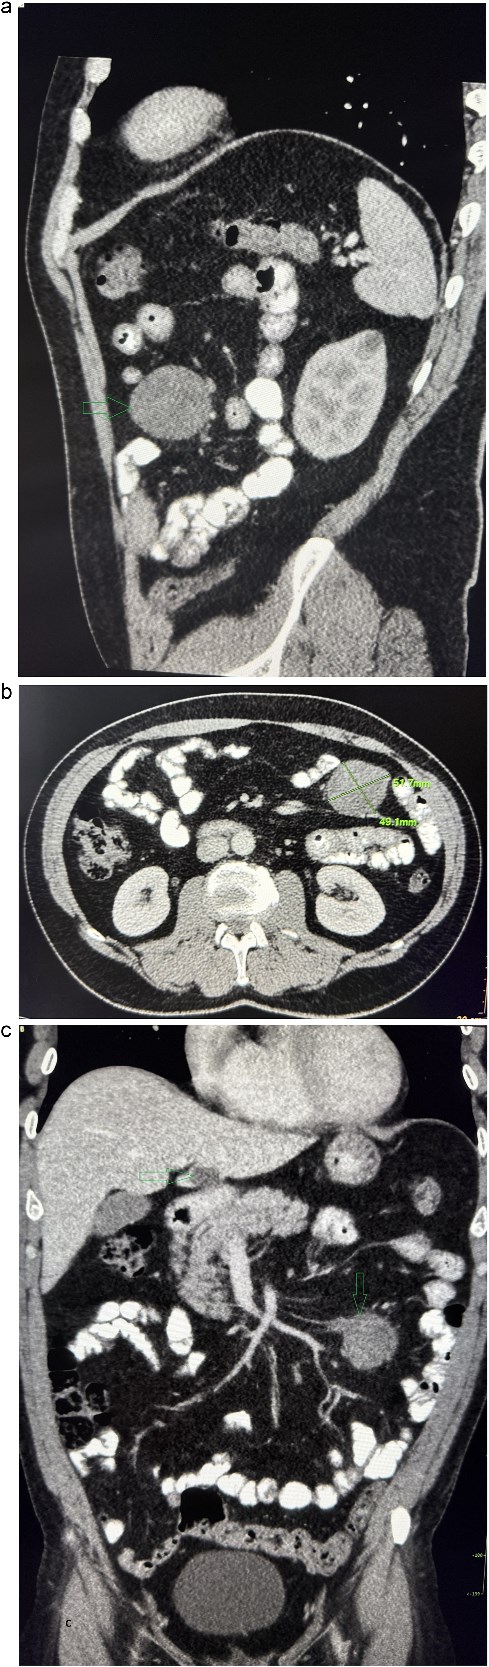

A 53-year-old obese polymorbid patient was initially examined by his general practitioner for 2 months of fatigue. Routine blood tests, physical examination, and X-rays of the lungs were unremarkable. Abdominal ultrasound examination diagnosed resistance in the left mesogastrium and no other pathology was found. The patient was referred to the surgical department for further examination. Abdominal examination was supplemented with computed tomography (CT), which diagnosed a circumscribed hypodense mass of 52 mm at the root of the mesentery in the left mesogastrium and suspected solitary metastatic liver disease (Fig. 1). Massive lymphadenopathy was considered in the differential diagnosis of mesenteric root resistance. Magnetic resonance imaging (MRI) was also indicated to verify the CT findings. MRI examination of the abdomen showed a tumor resistance of 58 × 45 × 45 mm in the root of the mesentery in the left mesogastrium and metastatic liver damage, including lymphadenopathy in the mesentery, was also excluded. The liver mass was diagnosed as a cyst (Fig. 2). According to MRI examination, a possible gastrointestinal stromal tumor, neurogenic tumor, or solitary fibrous tumor was considered as part of the differential diagnosis of mesenteric root resistance. The examination of oncological markers was negative. To investigate the etiology of resistance in the root of the mesentery, a biopsy of resistance was performed under CT control. The biopsy examination showed an ancient schwannoma with positive protein S100 and SOX10 on immunohistochemical examination. Based on the decision of the interdisciplinary indication seminar, the patient was indicated for elective surgery, laparoscopically assisted ileum resection with minilaparotomy in the left mesogastrium. The continuity of the ileum was then restored with a terminoterminal anastomosis sewn by hand seromuscularly in one row with a continuous monofilament suture. The operation went without complications and the patient was discharged on the fourth postoperative day for outpatient care with a fully restored intestinal passage. The tumor-resected ileum was sent for histological examination, which confirmed a schwannoma of the mesentery, which was completely removed (Fig. 3). The surgical wounds were mainly healed. No further dispensary for the patient was indicated.

Contrast-enhanced abdominal CT. (a) The sagittal section presents a tumor mass at the root of the mesentery in the left mesogastrium. (b) The axial section presents a tumor mass measuring 52×49 mm in diameter. (c) The coronal section presents a tumor mass at the root of the mesentery in the left mesogastrium and suspected metastatic liver lesion.